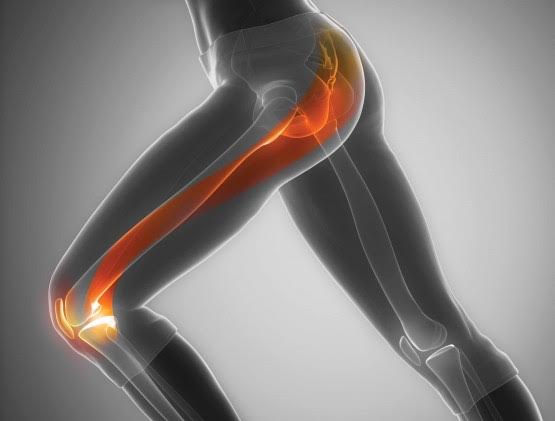

Σύνδρομο προστριβής λαγονοκνημιαίας ταινίας

Προκαλεί ένα σταδιακά αυξανόμενο πόνο στην έξω επιφάνεια του γόνατος λόγω της προστριβής του τένοντα της λαγονοκνημιαίας ταινίας (ενός μυ που ξεκινά από τη λεκάνη και καταλήγει στο γόνατο). Ο πόνος εμφανίζεται κατά τη διάρκεια του τρεξίματος, επιδεινώνεται και αρκετές φορές αναγκάζει τον δρομέα να σταματήσει. Μετά από ξεκούραση, ο πόνος υποχωρεί και εμφανίζεται ξανά όταν ο αθλητής επιχειρήσει να ξανατρέξει.